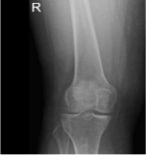

X-ray and MRI were presented in the office. Found vertical tear at the free edge margin of the posterior horn medial meniscus, with mild undersurface/free edge fraying of the body segment. Mild medial femorotibial compartment chondral loss. Mild patellofemoral compartment chondral wear, preferentially over the medial aspect of the compartment.

Lateral patellar tilt with mild lateral positioning of the patella. These findings may be seen in the setting of patellar malt racking. Features which may be seen in the setting of iliotibial band friction syndrome.

AP view